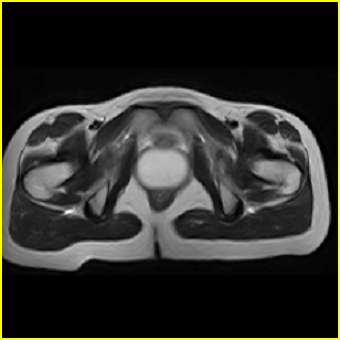

女、15岁、下腹疼痛2天,排尿困难1天。查体:处女膜闭锁,距处女膜约4至5cm处扪及一约5cm直径的圆形包块,张力较高,触痛明显、欠活动。b超提示子宫增大伴宫内增强回声团。

更正影像意见:阴道积血。

处女膜闭锁,阴道积血

处女膜闭锁,阴道积血,子宫积血.

处女膜闭锁,伴子宫及阴道积血.